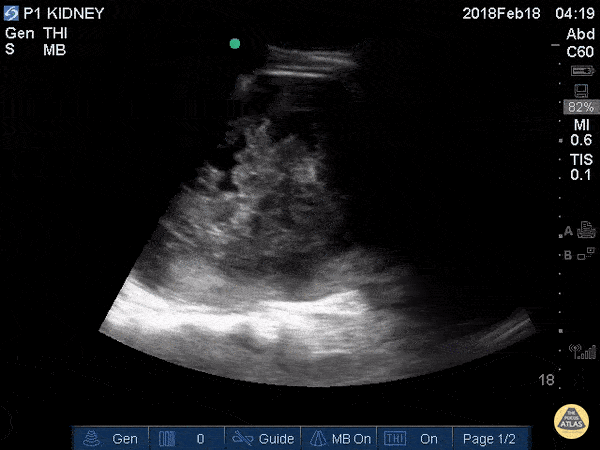

Renal/GU - Traumatic Kidney Hematoma

19M w/ hx “fell down stairs 1 week ago,” won’t provide additional details. Admitted to an outside hospital for renal laceration and subcapsular hematoma, here in ED today wondering if hematoma still present, asymptomatic; normal vitals. Greg Powell, MD